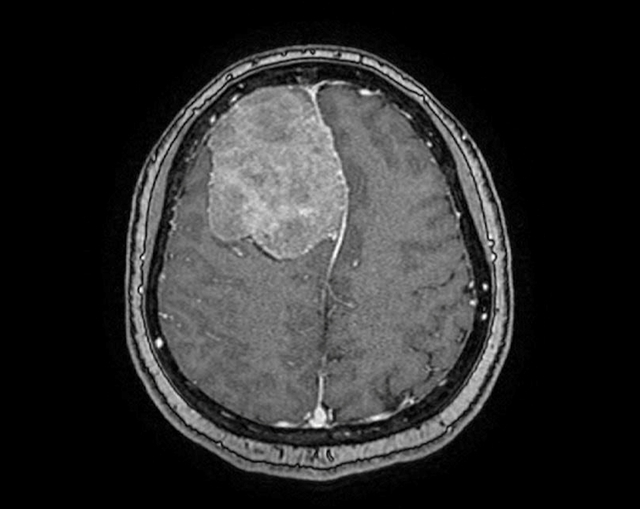

Chị Trịnh Nhật Khánh (nữ võ sư 45 tuổi, sống tại TP.HCM) thỉnh thoảng bị đau đầu nhẹ nên quyết định đi tầm soát đột quỵ tại Bệnh viện FV. Kết quả chụp MRI đã bất ngờ phát hiện ra một khối u màng não rất to, đường kính hơn 6cm, nhìn như một trái cam chèn ép gần 1/4 não.

Phim chụp MRI cho thấy một khối u lớn như trái cam sành trong não phải bệnh nhân

“Khối u phát triển trong thời gian dài, hộp sọ thích nghi với khối u nên khó được phát hiện. Khối u chưa ảnh hưởng tới chức năng thần kinh cấp cao, dù bệnh nhân thỉnh thoảng bị đau đầu. Tuy nhiên, trường hợp này cần được mổ sớm, vì nếu khối u lớn hơn nữa có thể gây ra các biến chứng nguy hiểm như động kinh hoặc thậm chí đe dọa trực tiếp đến tính mạng bệnh nhân”, BS.CKII Trần Lương Anh – Trưởng khoa Ngoại Thần kinh và Cột sống, nhận định.